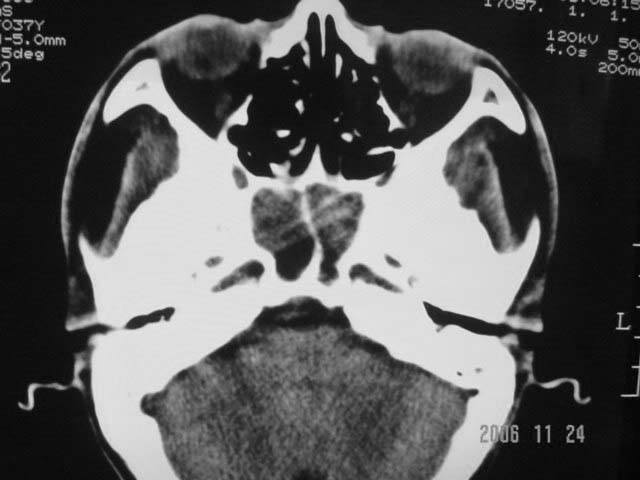

右侧鼻咽部软组织肿块,颅底骨质破坏,右侧颈部淋巴结肿大;诊断:鼻咽ca、右颈部淋巴结转移、颅底侵犯

右侧鼻口咽侧后壁不规则增厚,内可见密度不均匀性椭圆形软组织块影,边界欠清,咽旁间隙尚清.右颈部可见圆形软组织块影,鼻塞、耳鸣3个月,涕中带血2周,颈部可触及肿大淋巴结,考虑鼻咽癌,颈部淋巴转移.

右侧鼻咽后壁不规则增厚,内可见密度不均匀性椭圆形软组织块影,边界欠清,咽旁间隙尚清.右侧下方可见圆形软组织块影,双侧蝶窦呈均一高密度。

考虑:1、右侧鼻咽癌伴颈部淋巴结转移;

2、双侧蝶窦炎。

右侧鼻咽部软组织肿块,颅底骨质破坏,右侧颈部淋巴结肿大;诊断:右侧鼻咽ca伴右颈部淋巴结转移、颅底侵犯.

典型右侧鼻咽ca伴颈部淋巴结转移,中颅底骨侵蚀。

右侧鼻咽侧后壁不规则增厚,咽隐窝变钝,咽旁间隙变狭窄,见组织结节影[哨兵征],蝶骨似破坏,蝶窦内充塞软组织影,翼内外肌上分间隙模糊,右颈后三角区淋巴结肿大,右侧乳突增高气房消失。考虑鼻咽癌伴蝶窦侵犯及淋巴结转移,右侧浆液性中耳炎。其他恶性病变待排。